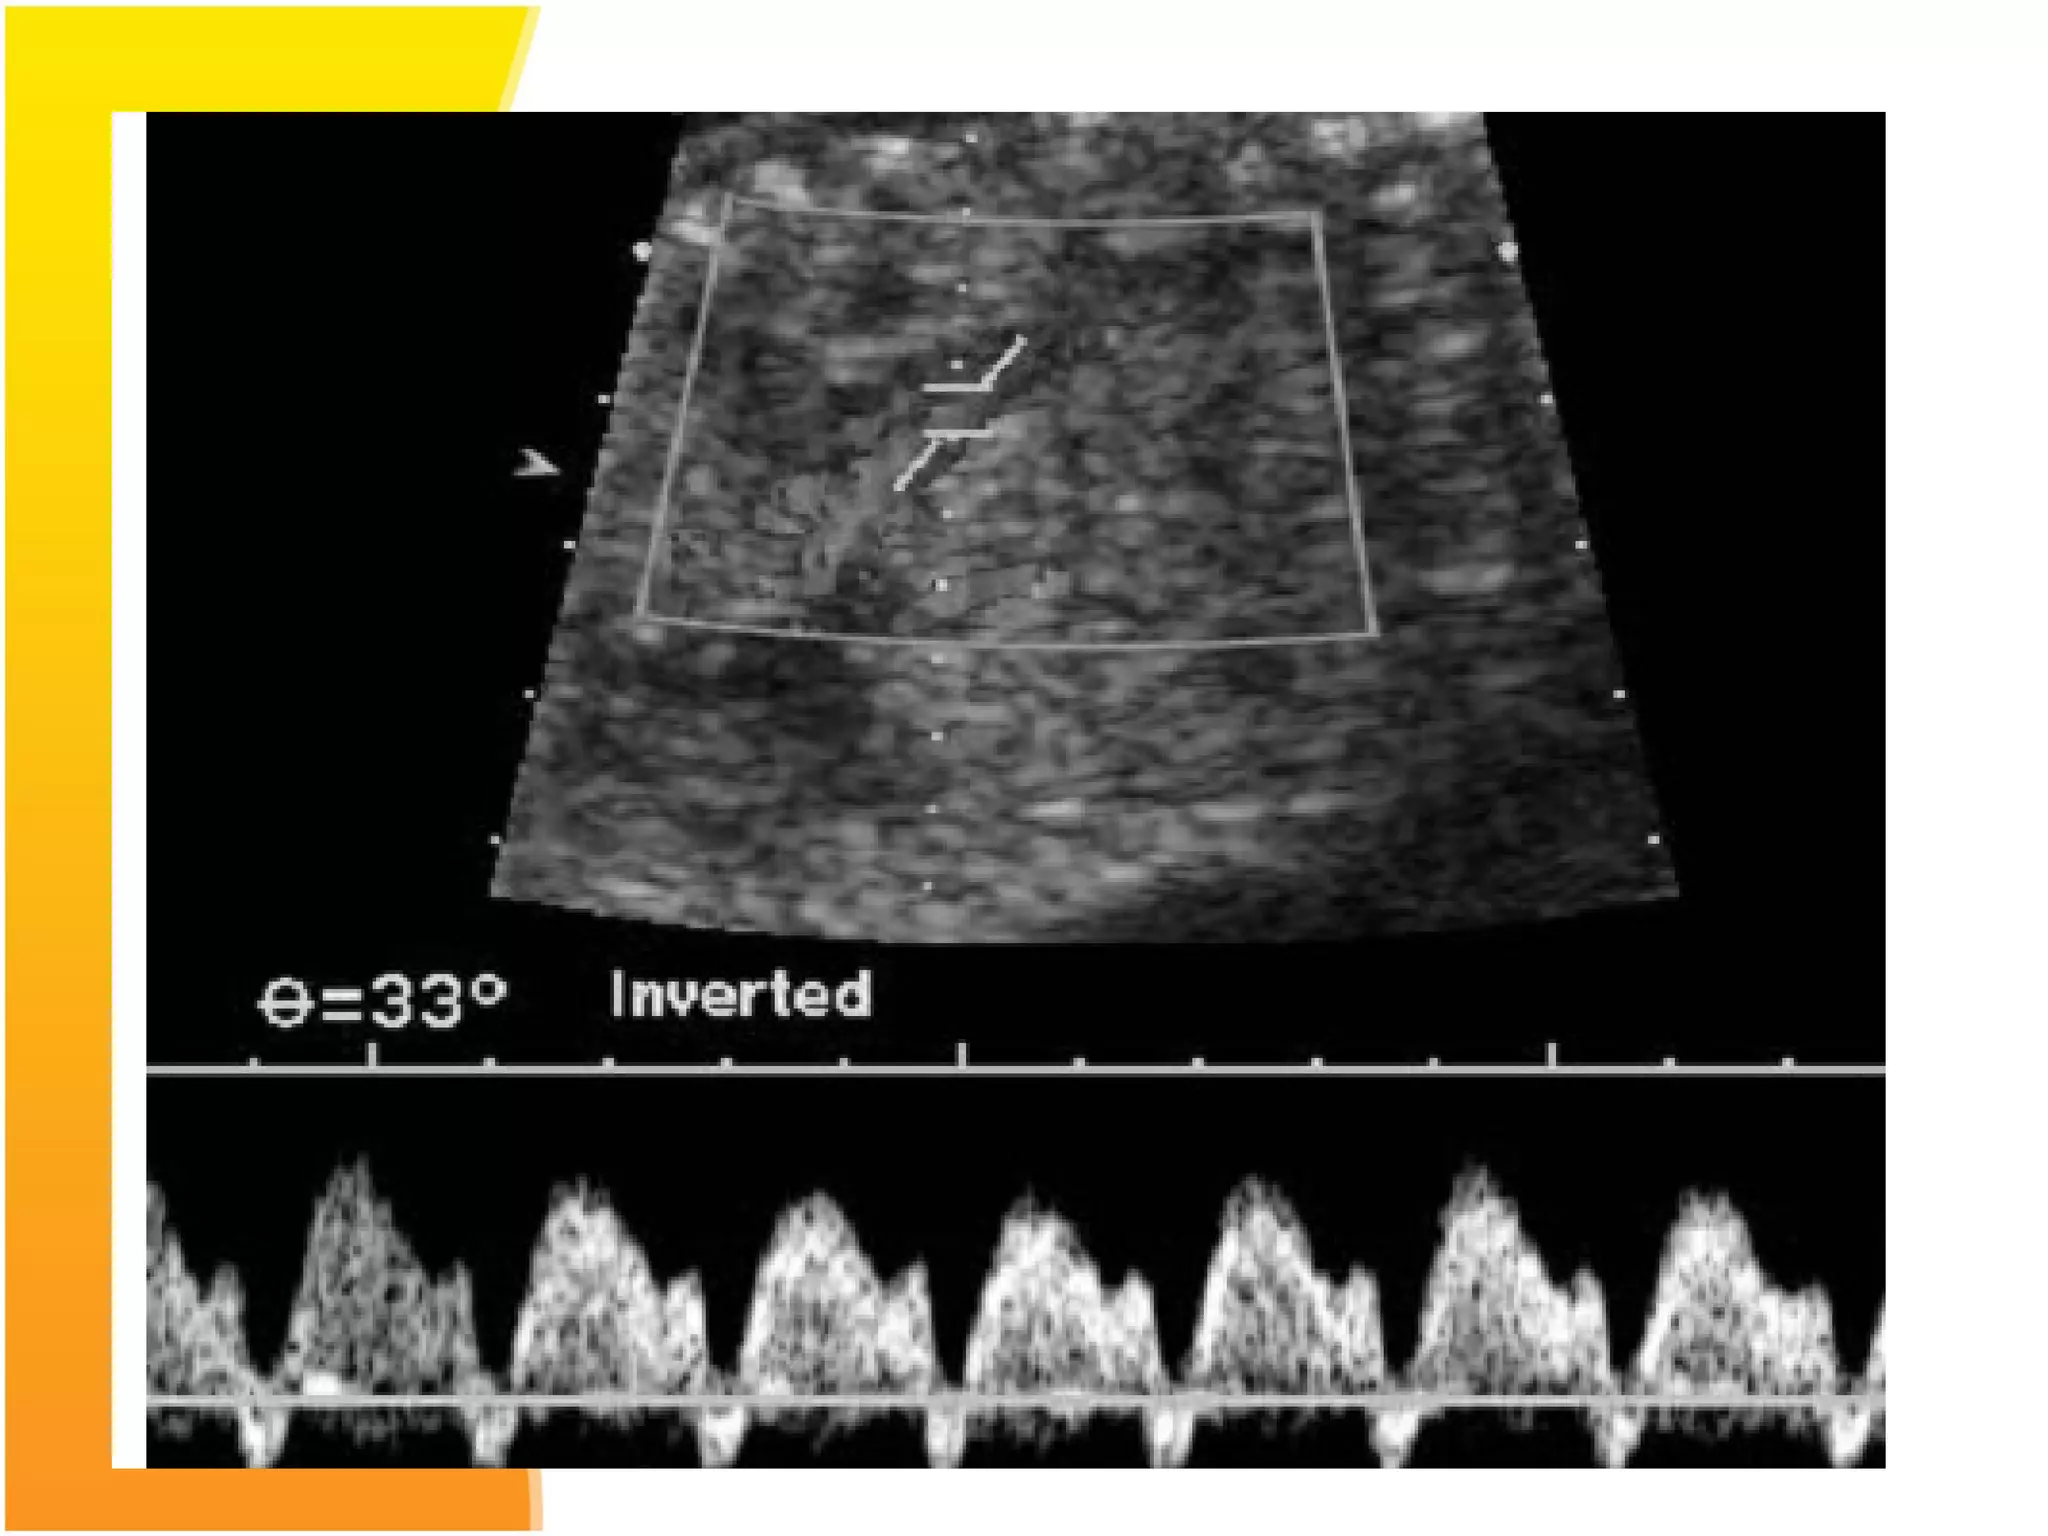

Normal Flow velocity waveforms of middle Cerebral Artery

Doppler

Cerebral artery doppler

Middle cerebral arterydoppler- in a normal fetus has relatively little flow during diastole. Increased resistance to blood flow in placenta results in redistribution of cardiac output to favour cardiac and cerebral circulations leading to increased flow in the diastolic phase with decreased S/D ratio.

Normal Flow velocitywaveforms of middle Cerebral Artery Doppler